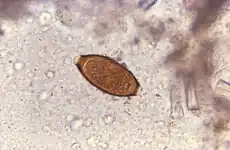

De zweepworm (Trichuris trichiura, synoniemen: Trichocephalus trichiuris, Tricocephalus dispar, Trichocephalus hominis) is een lichtgele tot witte parasiet. De vrouwtjes zijn 35-50 mm en de mannetjes 30-45 mm lang. Het voorste twee derde gedeelte tot en met de slokdarm is smaller dan het derde achterste, dikkere gedeelte, waardoor ze op een zweep lijken.[1] De vrouwtjes hebben een stomp eind en de mannetjes een gekruld eind. De bruine eieren zijn tonvormig en hebben aan de polen uitstulpingen. Ze leven van de uitscheidingen van het slijmvlies, waar ze met de voorkant in vastgeschroefd zitten.

Ei

De eieren worden met de ontlasting doorgegeven.1. In de grond gaan de eieren over in een tweecellig stadium 2, vervolgens ontstaat na meerdere delingen een veelcellig stadium 3. Uiteindelijk komt de L1-larve in het ei uit 4; en worden de eieren in 15 tot 30 dagen besmettelijk. Na inname (door met grond verontreinigde handen of voedsel) komen de L-larven in de dunne darm uit de eieren. 5 Vervolgens vervellen de larven nog vier keer, waarna ze volwassen zijn en zich in de darm nestelen 6. De volwassen rondwormen leven in de blindedarm en aansluitende dikke darm en zitten met de voorste delen in het slijmvlies vastgeschroefd. De vrouwtjes beginnen 60 tot 70 dagen na infectie eieren te leggen. De vrouwelijke rondwormen in de blindedarm scheiden dagelijks tussen de 3.000 en 20.000 eieren uit. Ze kunnen ongeveer 1 jaar in leven blijven.

Trichuris trichiura komt over de hele wereld voor met naar schatting 1 miljard menselijke infecties.[5][6][7][8] De besmetting komt voornamelijk in de tropen voor, vooral in Azië en in mindere mate in Afrika en Zuid-Amerika. In de Verenigde Staten is de infectie over het algemeen zeldzaam, maar komt vaak voor in het landelijke zuidoosten, waar 2,2 miljoen mensen besmet zijn. Slechte hygiëne wordt in verband gebracht met trichuriasis, evenals het binnenkrijgen van schaduwrijke,vochtige grond of voedsel dat mogelijk met uitwerpselen besmet is. Kinderen zijn bijzonder kwetsbaar voor infecties vanwege hun hoge blootstellingsrisico. Eieren bevatten onder de juiste omstandigheden van warmte en vocht ongeveer 2-3 weken nadat ze in de bodem zijn afgezet infectieuze L1-larven.